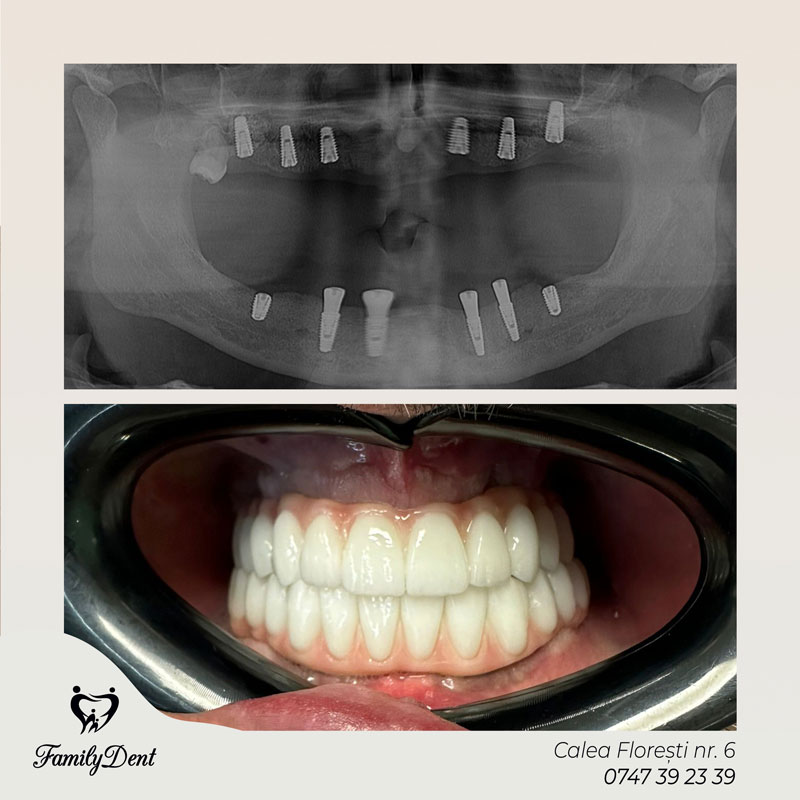

Reabilitări totale (All-on-4 și All-on-6): Aceasta este revoluția în stomatologia digitală pentru pacienții edentați total (care nu mai au niciun dinte pe arcadă).

All-on-4: Presupune fixarea unei arcade dentare întregi pe doar 4 implanturi dispuse strategic. Este o procedură extrem de eficientă, care adesea permite încărcarea imediată (primești dinți ficși în 24 de ore).

All-on-6: Similar cu All-on-4, dar utilizează 6 implanturi pentru a oferi o stabilitate sporită și o distribuție mai uniformă a forțelor masticatorii. Este recomandat în cazurile în care calitatea osului necesită un suport suplimentar pentru a asigura succesul pe termen lung.

Indiferent de sistemul ales, clinica noastră pune accent pe stomatologie digitală, folosind ghiduri chirurgicale care elimină eroarea umană, reduc timpul de intervenție și accelerează vindecarea.